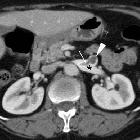

Post-thrombotic

aneurysmal dilatation of the hypogastric vein. The venous phase acquisition (d-h) showed the lesion (*) to enhance homogeneously and synchronously with venous vessels, consistent with aneurysmal dilatation of the proximal hypogastric vein. Urinary bladder (+).

aneurysmal dilatation of the hypogastric vein. Coronal (f) and sagittal (g,h) reconstructions confirmed aneurysmal dilatation (*) of the right hypogastric vein without signs of thrombosis. No abnormal dilatation, compression or thrombosis of the inferior cava, common and external iliac veins.